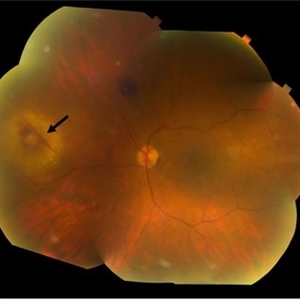

Fundus photograph of a 70-year-old woman with presumed sarcoidosis and sarcoid-associated choroidal granuloma.

Photographer: Christopher D Conrady, MD, PhD

Condition/keywords: sarcoid granuloma